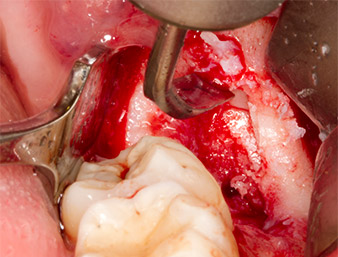

Tras una anestesia local y por conducción, el campo quirúrgico se abrió mediante los tejidos blandos para tener un acceso bucal-retromolar y se dejó expuesto (figura 3).

El tejido situado por encima del resto radicular no se había osificado por completo y constaba en su mayor parte de un tejido granulado con alteraciones inflamatorias (figura 4).

Con el fin de obtener material autógeno para el tratamiento posterior de la herida, se utilizó un inserto piezoquirúrgico (Piezomed B5) para obtener virutas de hueso sano del entorno del resto radicular (figura 5).